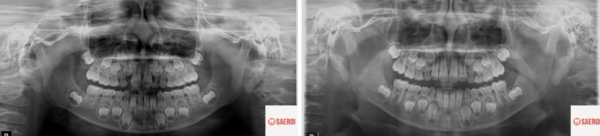

d1d86fa678bc9afe4b079fc3bd0a6047_1743647770_1262.png

정면 모습에서는 크게 잘못된 점을

찾기가 어렵습니다만

d1d86fa678bc9afe4b079fc3bd0a6047_1743647783_8723.png

웃을 때 보이는 치열의 모습이

위아래 앞니가 거꾸로 물리면서

심미적으로 바른 미소를 가지지 못합니다.

실제 구강 내 사진에서는

앞니 반대교합이 명확히 관찰됩니다.

위아래 앞니가 거꾸로 명확히 물리고 있으며

송곳니와 작은 어금니 부위의 반대교합도

동시에 관찰됩니다.

큰어금니 부위의 반대교합 경향도 보여서

위턱과 아래턱 폭의 부조화도 관찰됩니다.